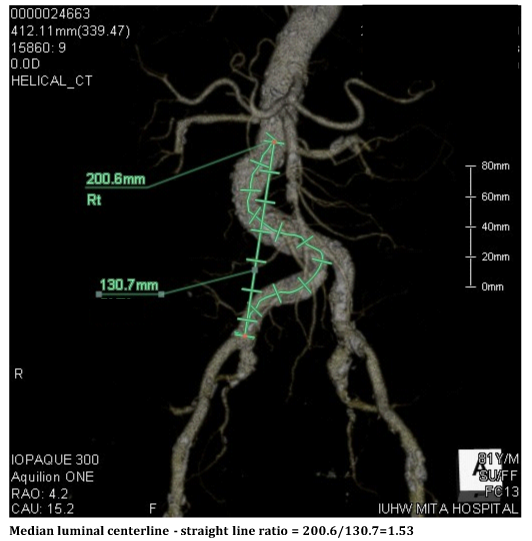

Wolf et al.1 reported that the difference between the actual distance and the straight line distance of the vessel, defined as the ratio between a median luminal centerline and a straight line on CT images, might be closely associated with the rate of procedural complications, including sheath kink or inability to straighten tortuosity. Calcification at a tortuous site could also serve as an additional predictive factor for these technical failures. If we had recognized prospectively that this case had a relatively high tortuosity index (1.52) and a severe calcification at the tortuous site (Figure 5), we could have paid more attention to the selection of the approach site, including consideration of a trans-radial or trans-brachial approach before the start of the procedure. The evaluation of the 3D CT examination was performed on another day, after the procedure, since this was an emergent case. Moreover, the presence of chronic kidney disease biased us against using those alternative approaches rather thana femoral one.8,9 Eventually, we waste da range of catheters and incurreda long fluoroscopy time.

Figure 5 Actual distance (left) and straight line distance of the vessel (right) on the 3D enhanced computed tomography images.